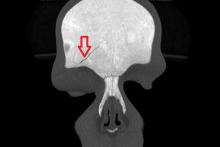

Przypadek 58: 6-latek po urazie głowy okolicy czołowej - zderzenie z kolegą.

Rozpoznanie: w wykonanym badaniu TK głowy - złamanie kości czołowej po stronie prawej. Szczelina złamania obejmuje łuskę kości czołowej (strzałka) oraz górną ścianę oczodołu prawego (nie pokazano na zdjęciach). Bez zmian pourazowych śródczaszkowo.